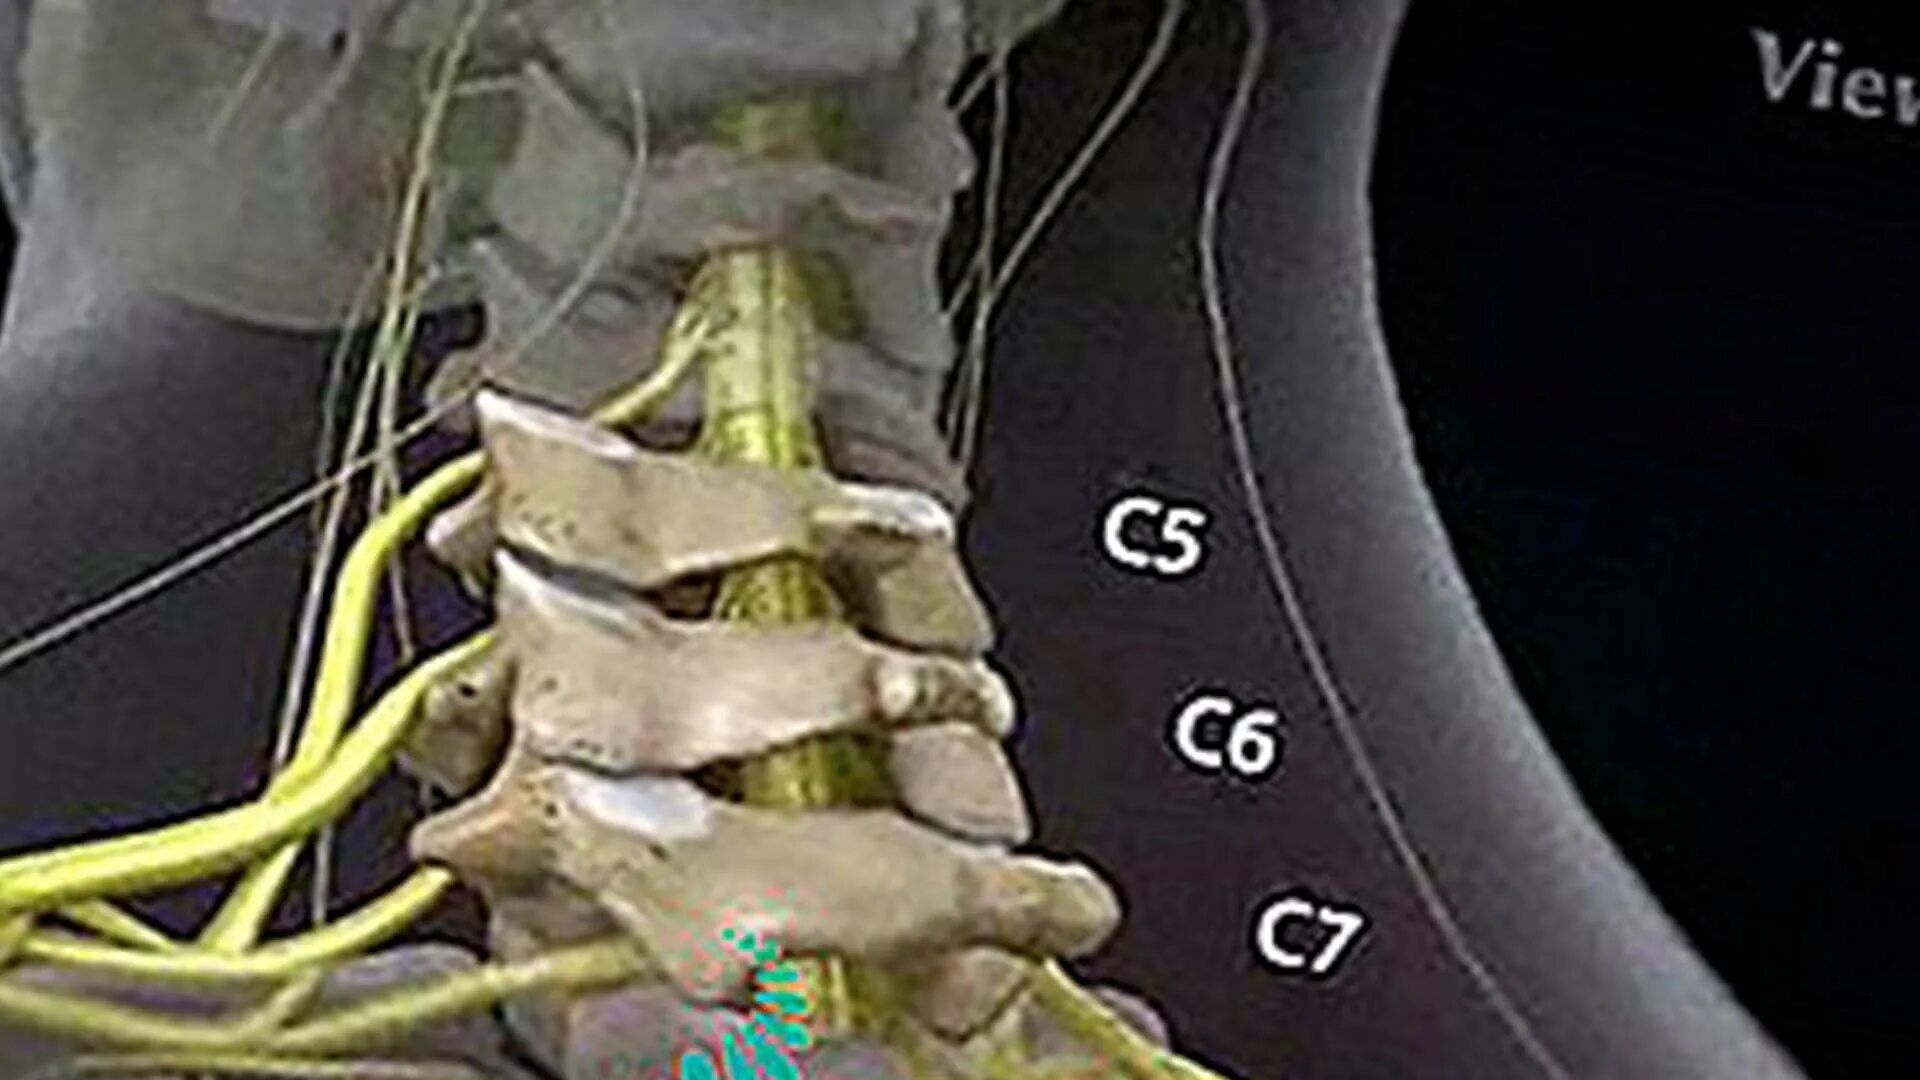

Протрузии дисков c6